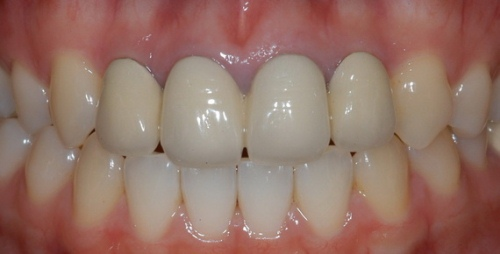

Таким образом я добился прикрепленной кератинизированной десны. Импланту на данный момент уже 5 лет и ни один виток импланта не оголился.

Это та основа, которую, я считаю, должны знать пациенты. Я ничего не скрыл от вас и рассказал все как есть. Если статья была интересная, поставьте лайк, а еще лучше подпишитесь на канал.